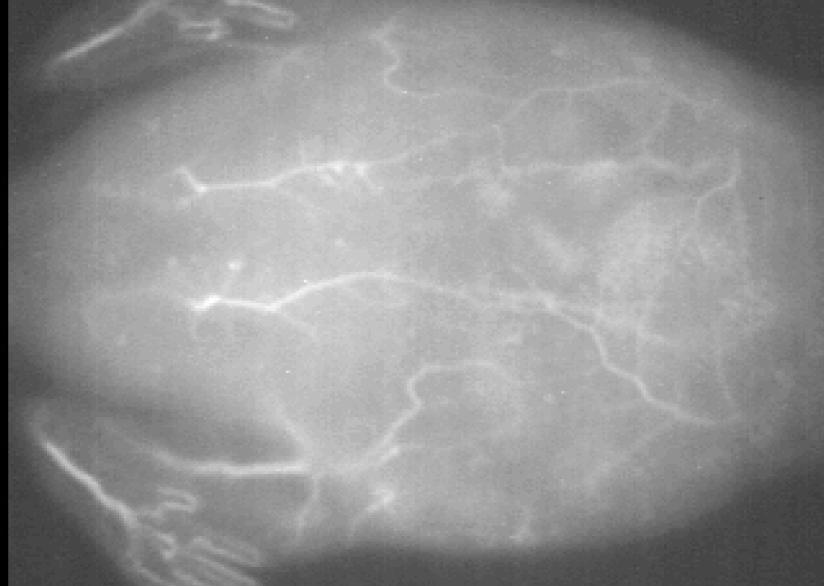

Whale and dolphin post-mortem imaging could breathe new life into marine conservation.

Researchers at City University of Hong Kong have developed a new, non-invasive imaging approach to examine the remains of beached marine mammals, like whales and dolphins. The approach, called virtopsy, was described in the journal Frontiers in Marine Science and can be used to determine the cause of death. It can also gather useful information about the animal before it died, such as its general health, as well as if it suffered human impacts, such as vessel collision or marine pollution.

These findings could help governmental agencies and stakeholders across the world implement more effective marine conservation policies to protect vulnerable marine mammals.

Virtopsy uses modern imaging techniques to examine dead marine mammal remains. It is performed before conventional necropsy, the animal equivalent of human body-opening autopsies, or can even replace it in some cases.

“Virtopsy appears to be more accurate, time-saving and non-invasive compared to conventional necropsy, with less risk of

disease contraction for veterinarians and human rescuers,” says CityU radiological clinician Brian Chin-wing Kot.

In Hong Kong, marine mammal remains are often found badly decomposed on beaches, making conventional necropsies very difficult. Virtopsies provide an effective alternative to examine external and internal structures.

Kot’s team has carried out virtopsies on beached marine animal carcasses since 2014. The Cetacean Virtopsy-driven Stranding Response Programme is conducted in collaboration with the Hong Kong Agriculture, Fisheries and Conservation Department, Ocean Park Corporation, and Ocean Park Conservation Foundation Hong Kong.

Kot and his team have performed virtopsies on more than 200 beached marine mammals using post-mortem computed tomography (PMCT) and post-mortem magnetic resonance imaging (PMMRI). The work shows that PMCT identifies bone lesions, foreign bodies, pathological gas formation and organ trauma better than conventional necropsy. PMMRI is

better at identifying soft tissue injury, organ trauma and non-traumatic pathology.

The team also found that PMMRI provides more information on decomposed brains than PMCT. Additionally, it should be used in conjunction with PMCT to detect soft tissue lesions and brain pathologies, as PMMRI alone is more prone to showing unwanted artefacts from gas and foreign bodies.

“Our study is a valuable reference for other stranding response programmes worldwide that are interested in integrating virtopsy or other modern diagnostic modalities into their routine workflow,” says Kot. “We hope our research helps humans realise a 'One Ocean, One Health' ideal,” a concept that promotes the understanding that human, animal and environmental well-being are interconnected.

The team is now expanding its work by partnering with governmental organizations and academic institutions in mainland China, Japan, Taiwan, Thailand, New Zealand, Switzerland, Costa Rica and the US for cetacean and sea turtle stranding investigations worldwide.

The team uses modern imaging techniques to examine dead marine mammal remains.